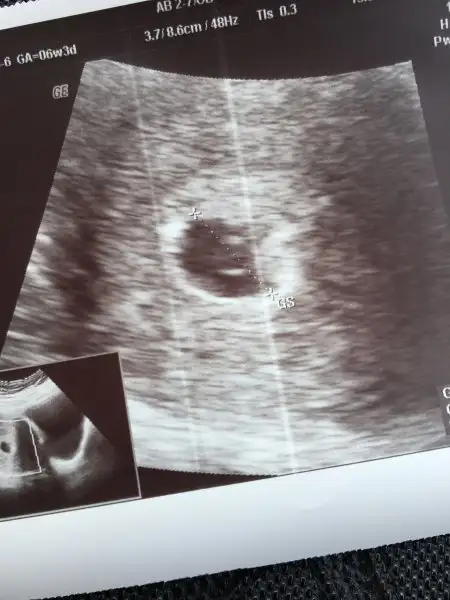

Merhaba canlar :)

Sabah doktora gittim herşey normal dedi , protein çıkmış ama bu teste güvenenem boşver iyisin dedi :))

Bebişi gördük kalp atımı alttan duyarız ama gerek yok haftaya karından bakalım dedi :) Çok şükür yani :))

Çok sebindim proteinin sorun olmamasına. Bu arada sadece teori ama kese yuvarlaksa kızdır derler:KK45: benim ilkinde ince uzundu oğlum oldu. Tabi hicbir bilimsel dayanağı yok :ıslık::ıslık:

Bunda ise sağda ve yuvarlak tam tersi yani bakalım bekliyorum bu teoriyi doğrulamak ya da yalanlamak için :D